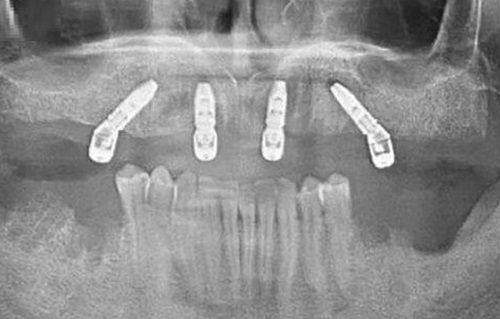

商丘交通医院中韩口腔本着与国内外接轨的理念,引进了多达数十项精良设备,包括进口HDX口腔三维CT、韩国原装进口种植体系统、瑞士种植体系统、美国普洋冷光美白仪、德国根管测量仪、韩国根管治疗仪等。 这些精良设备能够为医生提供更加正确、详细的口腔检查数据,帮助医生制定更加科学、合理的治疗方案。例如,进口HDX口腔三维CT能够清晰地显示患者口腔的三维结构,为种植牙手术、牙齿矫正等治疗提供重要的参考依据。 同时,医院还注重设备的维护和更新,确保设备的正常运行和性能稳定。医院定期对设备进行检查、保养和维修,及时更换老化或损坏的部件,以确保设备的精度和可靠性。